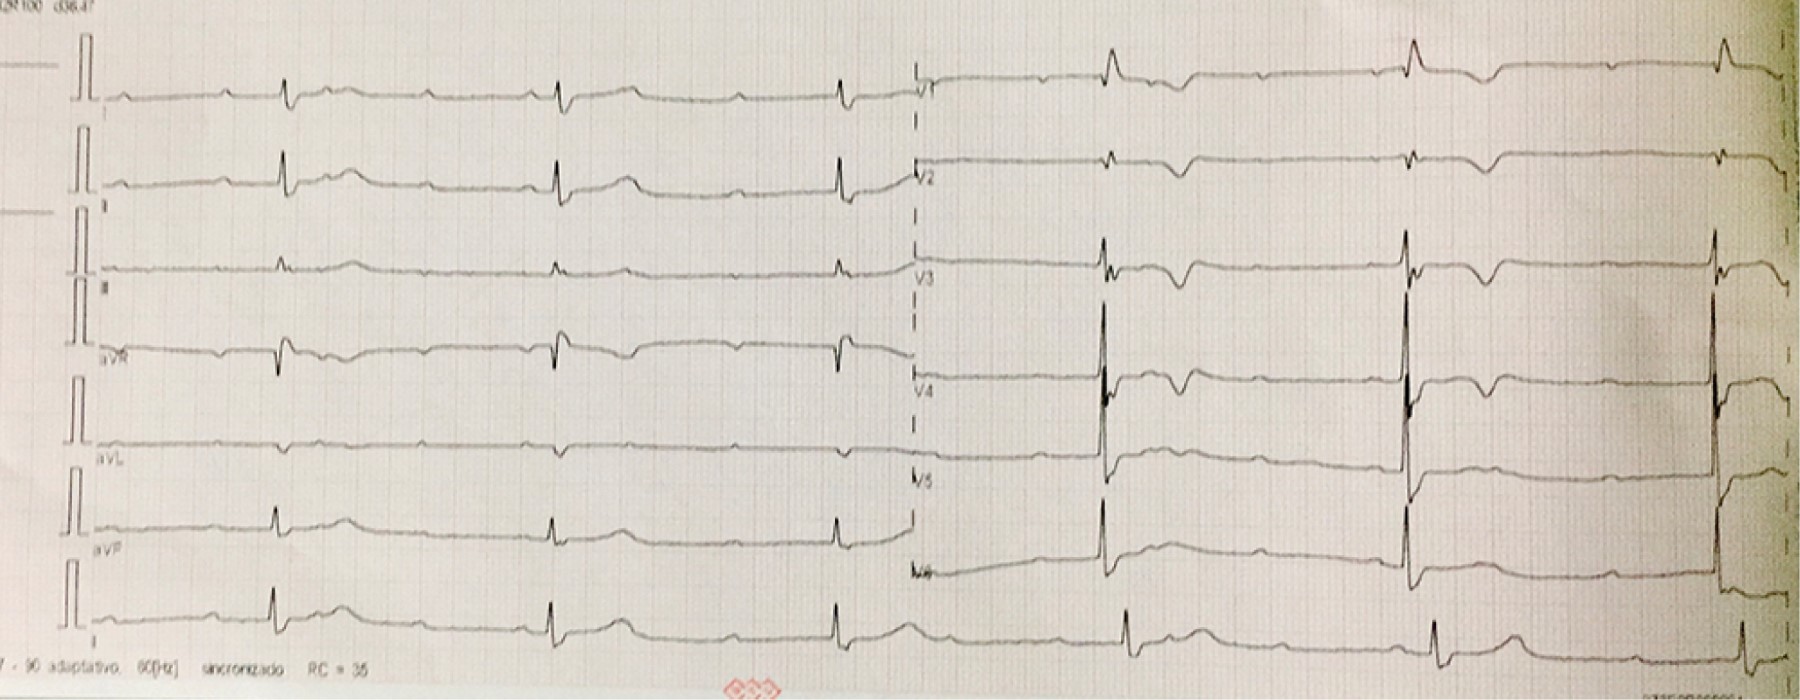

Pacemaker implantation through the persistent left superior vena cava due to the absence of the right superior vena cava. Report of a case

Introduction: the persistence of the left superior vena cava (PLSVC) has a prevalence of 0.21% in the general population. Case presentation: 67-year-old male diagnosed with third-degree AV block, requiring pacemaker placement. However, due to the absence of a right superior vena cava, corroborated by CT angiography, a definitive pacemaker was placed through a persistent left superior vena cava. Conclusion: the persistence of the left superior vena cava (PLSVC) is the most common thoracic venous anomaly. It can cause a number of clinically significant symptoms, even in a heart with normal anatomy. Pacemaker placement makes electrode fixation difficult due to tortuous travel.

Figure 1